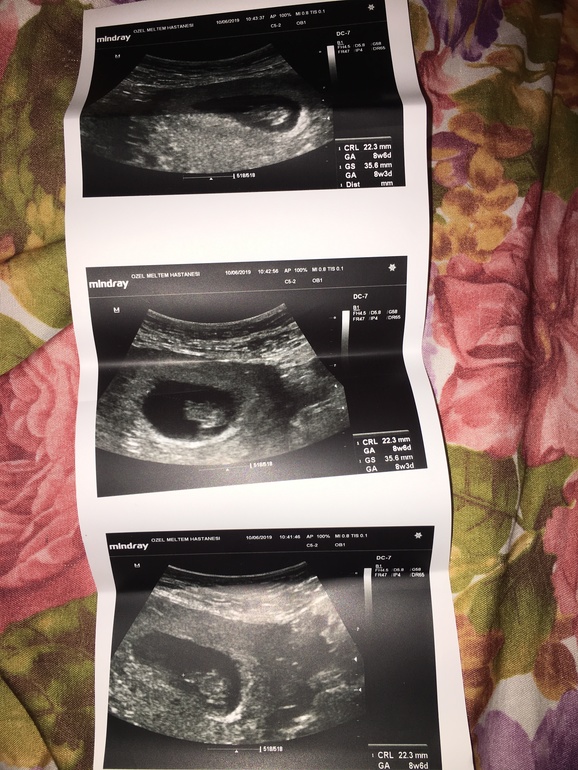

Сегодня была на узи. Малыш ттт норм. Сердечко стучит. Гематом нет, все ок.

По ктр эмбрион на 8 нед 6 дн (даже на 2 дня опережает срок).

НО. Плодное яйцо на 8 нед 3 дн. Получается отстает от эмбриона на 3 дня🤷🏼♀️.

пя 35,6 мм

ктр 22,3 мм

Фото узи. Вроде по фото место малышу хватает...